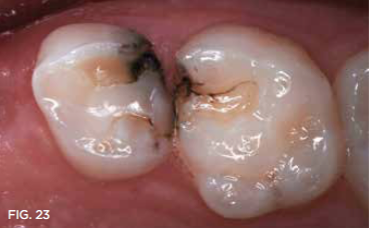

Case 6. This 11-year-old had a small fracture of a mesio-occlusal restoration of his primary second molar and marginal caries develop in the long-term Class II restorations in that tooth and the adjacent primary first molar. A bite wing radiograph revealed that those teeth would be exfoliating within 12 to 18 months. SDF was painted around the involved tooth surfaces, and continuing damage from the recurrent caries lesions ceased. Only one SDF coating was used; the teeth were photographed 8 months later (Figure 23).

Fig 23. 8 months after single SDF applications in previously restored teeth in an 11-year old.

Fig 23